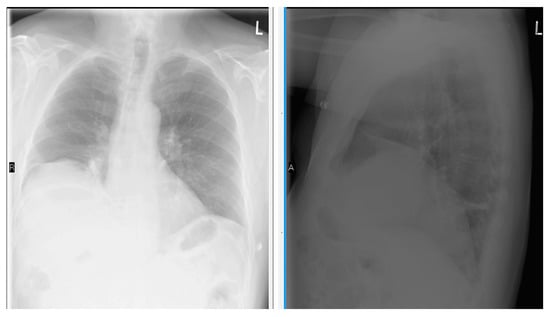

- Chetta, A.; Rehman, A.K.; Moxham, J.; Carr, D.H.; Polkey, M.I. Chest radiography cannot predict diaphragm function. Respir. Med. 2005, 99, 39–44. [Google Scholar] [CrossRef] [PubMed]

- Nason, L.K.; Walker, C.M.; McNeeley, M.F.; Burivong, W.; Fligner, C.L.; Godwin, J.D. Imaging of the diaphragm: Anatomy and function. Radiographics 2012, 32, E51–E70. [Google Scholar] [CrossRef] [PubMed]